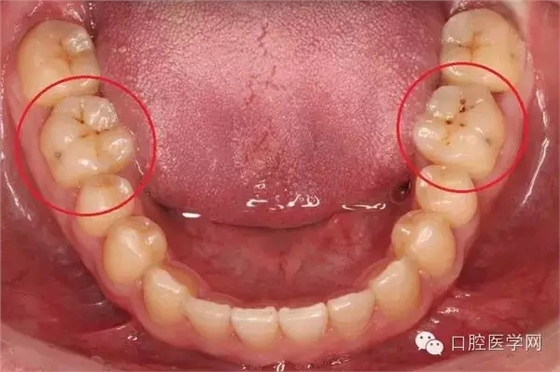

另一種則是牙齒出現(xiàn)了或深或淺的齲壞,從外面看就表現(xiàn)為一個(gè)黑點(diǎn),通常位于窩溝點(diǎn)隙(牙面上點(diǎn)狀或線狀凹陷)。齲齒的罪魁禍?zhǔn)资强谇恢械哪承┘?xì)菌,但它們破壞牙齒也是需要時(shí)間的,從初期的變色到最終形成齲洞,通常需要1年半到兩年。在此期間,我們多留心自己的牙齒,完全可能把齲壞扼殺在萌芽階段。如何才能及時(shí)發(fā)現(xiàn)這種隱匿的蛀牙呢?找位好牙醫(yī),半年檢查牙齒!

一旦確認(rèn)牙齒上的小黑點(diǎn)是齲齒就應(yīng)該盡早修補(bǔ),以阻止病變的發(fā)展。如果任由其繼續(xù)發(fā)展就會(huì)變成明顯的齲洞,這時(shí)患者會(huì)對(duì)冷熱酸甜等食物刺激敏感;當(dāng)損傷進(jìn)一步到達(dá)牙髓(即老百姓說(shuō)的“牙神經(jīng)”),就會(huì)疼痛難忍,嚴(yán)重影響日常生活。臨床上見(jiàn)到很多人都會(huì)等到牙痛得受不了,才到醫(yī)院就診。這時(shí)通常不能靠單純補(bǔ)牙來(lái)解決問(wèn)題,可能還要做根管治療甚至拔除患牙、進(jìn)行假牙修復(fù),費(fèi)時(shí)費(fèi)力又費(fèi)錢(qián),人還遭罪,可謂“小洞不補(bǔ),大洞吃苦”。